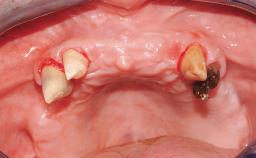

Surgical treatment of a 68-year-old female patient who experienced failure of her conventional bridge in the right maxilla. After removal of the compromised abutment teeth and a healing period of 6 weeks, a sinus floor elevation procedure using the lateral window technique and a composite graft to correct the insufficient bone height is carried out.

Two dental implants are placed in the same surgical session. The case concludes with the presentation of the final fixed dental prosthesis with a distal cantilever unit.

The 1-year follow-up radiographs demonstrate successful sinus floor elevation and stable bone crest levels around both implants, leading to a favorable long-term prognosis of the implant-supported prosthesis.